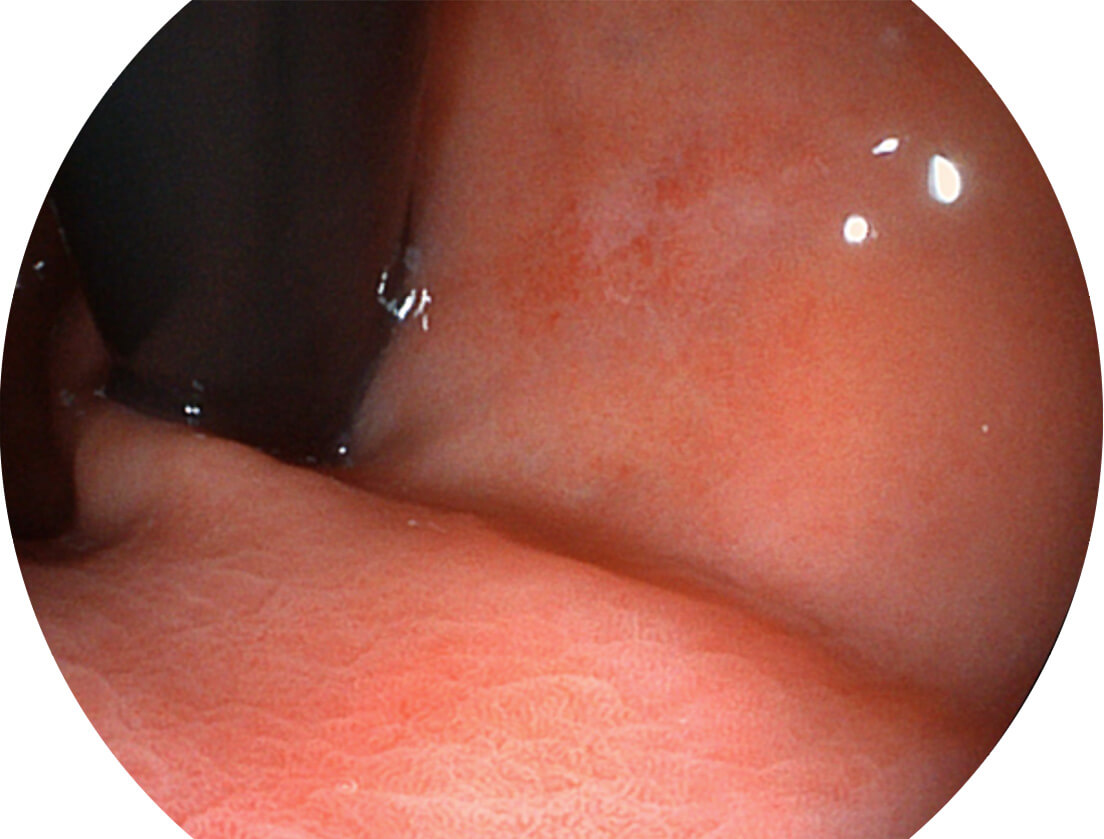

图像具有高亮度、高黏膜血管颜色对比度的特点,且不改变粘液、食物残渣、粪便的基本颜色,可在中远景下进行观察,助力消化道早期疾病的诊断。

强调浅层黏膜结构的同时,保证照明亮度和提升浅层微血管与中层血管颜色对比度,病变边界更清晰。

• VLS-55系列四波长LED光源

采用光路合束技术,光谱自由度高,实现了更丰富的照明模式,染色模式SFI及VIST,从远景到近景,助力消化道早期疾病诊断。